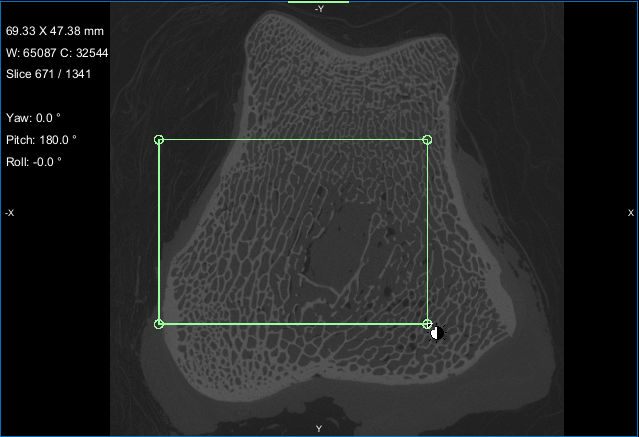

This Bone Analysis tutorial provides step-by-step instructions for segmenting a proximal femur and for computing vector-based fields of anisotropy and scalar-based maps of volume fraction. Additional topics in this tutorial describe how to compute high-resolution maps from data sub-volumes and how to evaluate the computed maps.

Screen capture of the completed tutorial